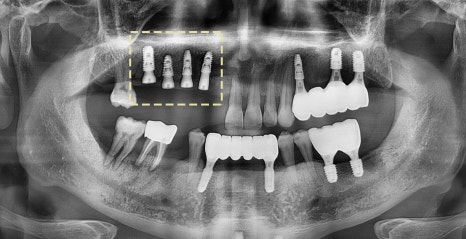

아래 사진을 보면

1. 잇몸치료로

치석과 치태를 말끔히 제거했으며

2. 픽스쳐 식립으로

어금니의 기능을 회복시킬 수 있었습니다.